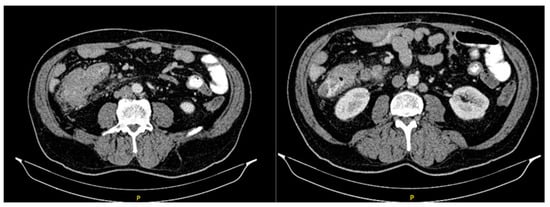

The initial abdominal ultrasound verified changes in the liver parenchyma suspected of metastatic lesions. The abdomen and pelvis CT scans showed multiple focal nodal areas of the liver parenchyma highly suspicious for liver metastases. In the area of the caecum, there was an infiltrative thickening of the wall of the terminal ileum area with associated luminal narrowing, reactive changes of perivisceral adipose tissue, and reactive lymphadenopathy (Figure 2). The proximal endoscopy findings were normal.

Figure 2.

Abdominal CT scan showing tumor mass.